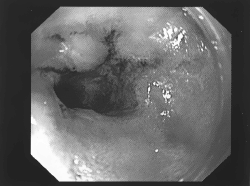

діагностика

Виявляється патологія після дослідження біоптату слизової, яка проводиться в процесі ФГДС. У препараті виявляють характерні змінені клітини, які продукують сульфамуцін. Ця речовина здатна абсорбувати на собі канцерогени, які провокують розвиток онкології.

Також клітини змінюють склад своїх антигенів: з'являється раково-ембріональний антиген (свідоцтво зниження диференціювання клітин), підвищений рівень якого виявляють у крові. В результаті проведених досліджень виставляється діагноз, в формулюванні якого враховуються розміри і місце знаходження метаплазії, наприклад, вогнищева кишкова метаплазія слизової антрального відділу шлунка.